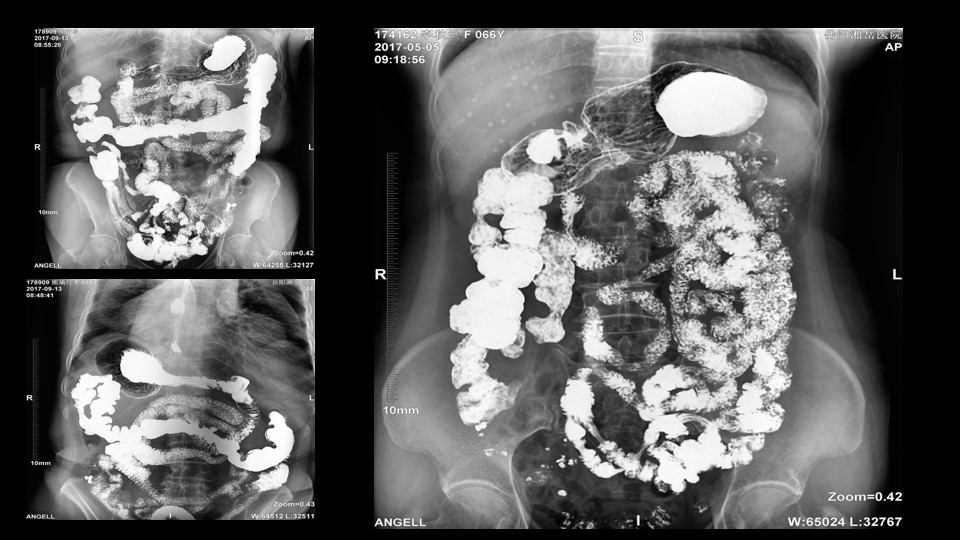

会议开始,岳阳市医学会放射分会副主委、湘岳医院放射科蔡雨主任,结合自身在放射影像的20多年经验,为参会嘉宾分享了动态DR在消化道造影中的应用价值。作为动态DR用户,蔡雨主任结合动态DR的实际拍片与操控经验,分享了动态DR技术在相关群体疾病检查上的独到优势和人文关怀。蔡雨主任说到:“随着内镜技术的发展以及CT、MR的发展,消化道造影在减少,但是这并不意味着消化道造影的价值在下降。以老年人为例,很多老年群体都患有严重的心肺疾病、或者消化道畸形,很多老年人本身就有糖尿病、高血压等等综合疾病,传统内镜的检查对于这类群体来说是一件难以忍受的痛苦,而动态DR的多项创新技术让这类群体的消化系统疾病筛查变得更为人性和精准。任何一个好的消化道造影,一定是患者、诊断医生、临床医生三方满意的结果。亿万28入口网页版-亿万28网页在线玩-万28官网下载最新版-亿万e网址pg-亿万28pg电子-亿万28赏金女王-亿万28娱乐科技动态DR技术利用900万像素高清拍片、大幅面透视、高清点片、视频保存与回放等核心功能,完全满足临床对消化道气钡双重造影检查的需要。图像质量全面超越以往模拟胃肠机、影增数字胃肠机”。蔡雨主任全面演示了动态DR在食道造影、上消化道造影、小肠双对比造影、结肠气钡双对比造影中的应用,通过动态DR可以清晰获得临床诊断和评估的图像依据。

▲蔡雨主任使用动态造影图像示例